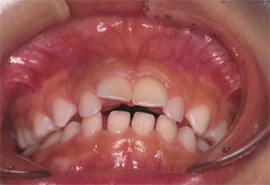

(1)上顎前突:上の前歯が前方に出っ張る。

![]() |

【写真1】 5歳児の親指しゃぶりによる上顎前突(前歯2本)の突出がみられる。 |